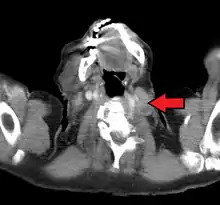

The supraclavicular lymph nodes can be felt in the supraclavicular fossa, shown here.